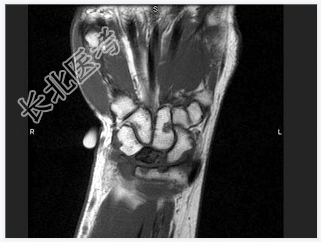

- [材料题] 女,41岁,纺织工,腕部疼痛无力数周。

- 简答题1、结合CR和MR,最可能的诊断是?

- 简答题2、右侧月骨缺血坏死的常见原因是什么?

- 简答题3、右侧月骨缺血坏死的早期症状有哪些?

- 简答题4、右侧月骨缺血坏死的治疗方案有哪些?